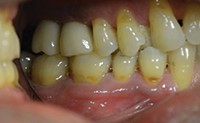

پس از 3 هفته بیمار برای ارزیابی و تاثیرات نهایی به کلینیک برگشت. تاج های موقت برداشته شدند و پیکاپ قالب های انقباض بافت (TRIPs) در محل قرار گرفت (شکل 16). قالب نهایی با استفاده از ترکیبی از مواد قالب گیری وینیل پلی سیلوکزان سنگین و سبک (Identium [Kettenbach LP]) (شکل 17) گرفته شد. هنگامی که این قالب ها از دهان خارج شدند، آنالوگهای تک بخشی ایمپلنت دوباره در TRIPs قرار می گیرند. قالب های چهارگوش بالا و پایین (Futar [Kettenbach LP]) برای ساخت ترمیمهای PFM فردی به آزمایشگاه فرستاده شد (شکل 18). تاج های موقت برداشته شدند و سپس بیمار مرخص شد.

شکل 19. ترمیم نهایی PFM در محل.

پس از حدودا 2 هفته، بیمار برای جابجایی نهایی ترمیم ها مجددا بازگشت. پس از خارج کردن تاج های موقت، تمام مواد چسبی موقت باقی مانده از پایه ها پاک شدند و تاج های مورد نظر برای انطباق مورد بررسی قرار گرفتند. تنظیمات اکلوزال انجام شد و تاج ها با چسب (Improv [Alvelogro]) محکم شدند (شکل 19).

چسب های اضافی خارج شده و با رادیوگرافی تأیید شدند (شکل 20).